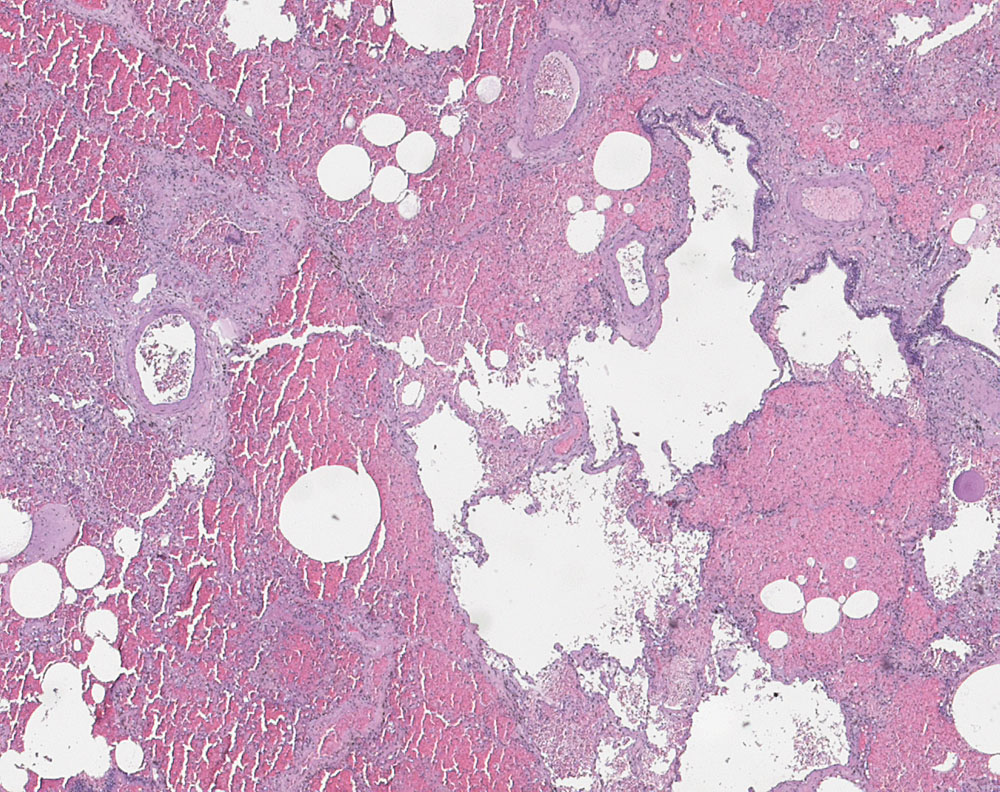

pulmonale Kapillaritis bei Kollagenose

Diffuse intraalveoläre Blutungen. Die Bronchiolen enthalten kein Blut.

Autopsiebefunde: Karnifizierende Aspirationspneumonie. Diffuse alveoläre Blutungen in allen Lungenlappen. Rezidivierende extrakapilläre Glomerulonephritis. Rechtsbetonte Myokardhypertrophie. Sklerose der Submukosa des Ösophagus.

72 jährige Patientin mit akutem Nierenversagen und pulmonalen Blutungen.

1. Verdacht auf ANCA-assoziierte Kleingefässvaskulitis mit Befall von Nieren und Lunge. ANCA-MPO positiv.

2. Verdacht auf Aspirationspneumonie

3. Hochgradiger Verdacht auf limitierte systemische Sklerodermie bekannt seit einem Jahr

Es handelt sich hier um eine mit einer systemischen Sklerose assoziierte, MPO-ANCA positive Vaskulitis mit pulmorenalem Syndrom (extrakapilläre Glomerulonephritis und pulmonale Hämorrhagien mit Kapillaritis). Diese Assoziation wurde in der Literatur bereits mehrfach beschrieben. Semin Arthritis Rheum. 2011 Oct;41(2):223-9. Anti-neutrophil antibody associated vasculitis in systemic sclerosis. Arad U et al. PMID: 21277620